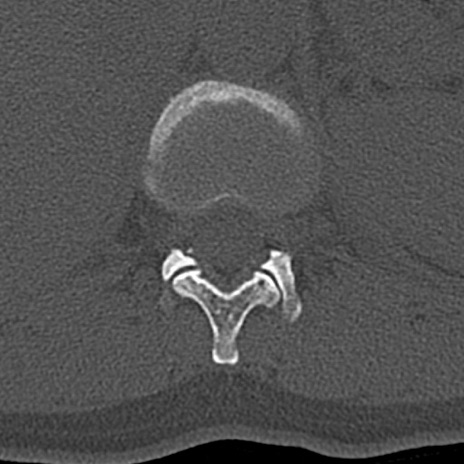

【整形】TIPS症例4 腰椎CT(横断像)

腰椎CT

横断像と矢状断像